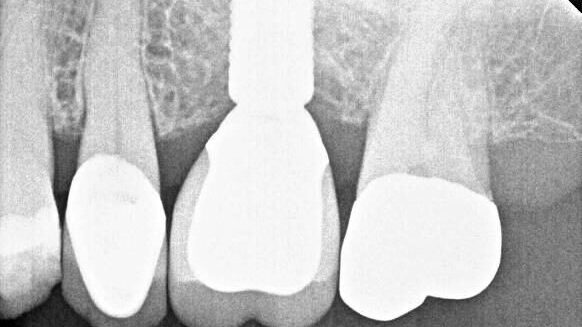

This case showcases an example of Abutment screw failure resulting from off axis loading on a lingually inclined maxillary implant.

This case illustrates how wrong restorative components led to two abutment screw failures in two years leading to an abutment screw rescue.